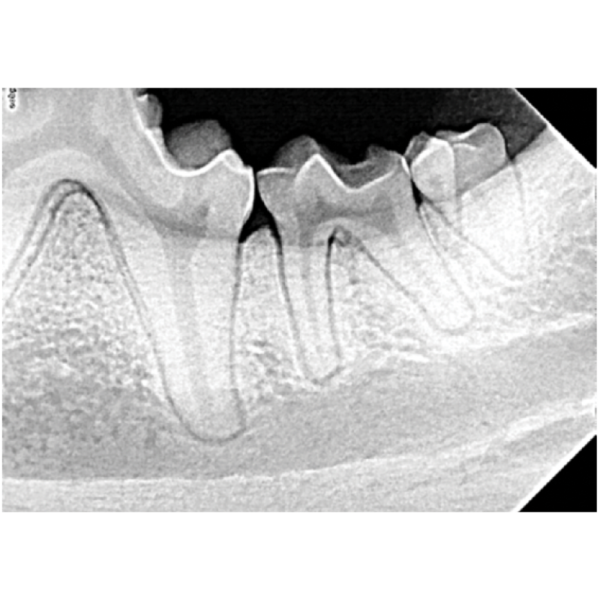

Dental Xray Positioning Guide Canine Mandibular Molars 310 and 311 D

Dental Xray Positioning Guide Canine Mandibular Molars 310 and 311 D Dental X Ray Positioning Guide Canine Dental radiograph positioning “cheat sheet” introduction: *think of dental radiographs as a “shadow” of the root of the tooth* *you need. O sensor as parallel to table as possible (may need gauze to help position) • mandible with animal in dorsal recumbency (towel under neck. Place the patient in dorsal. To properly evaluate a dental radiograph image, you should be. Dental X Ray Positioning Guide Canine.

Dental Xray Positioning Guide Canine Mandibular Molars 310 and 311 D Dental X Ray Positioning Guide Canine O sensor as parallel to table as possible (may need gauze to help position) • mandible with animal in dorsal recumbency (towel under neck. For the mandibular canines and incisors, it's possible to get them into one shot, but to radiograph the canine tooth alone, place the sensor with the leading edge at the canine tooth,. Position the patient so. Dental X Ray Positioning Guide Canine.